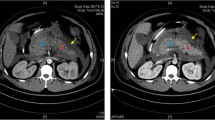

In the present study, a 28-year-old female Han Chinese with her first pregnancy during the third trimester was admitted to our emergency room and diagnosed with acute pancreatitis. Several days prior to this episode, lactescent levels were elevated in her serum however this was not noted. When admitted, blood tests revealed extremely high serum levels of HTG (TG 79 mmol/l, while normal ranges are 0.0-1.7 mmol/l). Following immediate cesarean section, she gave birth to a healthy baby girl and then was treated with dietary restriction and supportive treatment for 28 days, then discharged from the hospital.

Meanwhile, the 58-year-old mother was also admitted to our hospital with a diagnosis of acute pancreatitis. Including this hospitalization, she had two previous episodes of abdominal pain and was diagnosed with acute pancreatitis after intake of fatty food. The plasma levels of total triglyceride were 25.4 and 16.3 mmol/l, respectively at these episodes. The proband’ mother was married to her father at age 22 through a consanguineous marriage. Because these two patients presented with severe HTG and acute pancreatitis, they were strongly suggestive of an inherited condition.

Discussion

In the current study, we showed two-related patients who manifested massive HTG and acute pancreatitis with a low LPL post-heparin activity. Both probands present the same LPL genotype with a compound heterozygote for a known missense mutation A98T in exon3 and a novel missense mutation L279V in exon 6 of LPL gene. Moreover, the novel mutation L279V was also found in one of 70 HTG individuals.

To date, the majority disease-causing LPL gene mutations occurs at exon 4, 5 and 6 residues (117–312), which constitute a large N-terminal domain (residues 1–312) of the enzyme and this region is the most conserved and important for LPL catalytic functions[12]. Exon 6 (residues 232–313) encodes two structurally relevant disulfide bridges (Cys278-Cys283 and Cys264-Cys275) for the binding of heparin[13]. The novel mutation L279V constitutes one of these two disulfide bridges (Cys278-Cys283), which is important for catalytic function of heparin binding. Both patients had low post-heparin LPL activity but normal levels of mass, further demonstrating this possibility.

Patients with two defective LPL alleles will have no or markedly reduced LPL activity, thus, homozygous or compounds of heterozygous mutations lead to severe HTG while one defective LPL allele may have normal to moderately increased blood levels of fasting triglyceride[15–17]. In this study, the mother and daughter had the same LPL genotype with compound heterozygous mutations of A98T and L279V; thus, both manifested massive HTG and acute pancreatitis. In contrast, the family members who carried a single mutation either A98T or L279V, only presented mild HTG and had no history of acute pancreatitis. Moreover, another unrelated HTG individual, who had the compound heterozygote L279V and a known GPIHBP1 mutation, suffered from a severe HTG and acute pancreatitis.